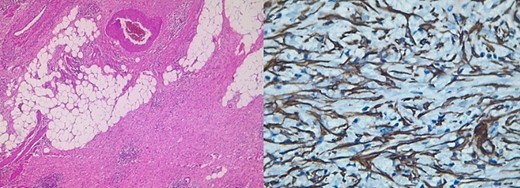

Pathology reported a 10 × 6 cm tumor. It expanded from the cecum into the ileocecal valve and had a soft exterior. Microscopically, it was formed by multiple myofibroblastic spindle cells with borderline malignancy. Numerous plasma cells and lymphocytes were also seen (Fig. 2). Immunohistochemistry was positive for actin and ALK (Fig. 3). Margins were free of tumors, and all lymph nodes were negative for invasion. Inflammatory myofibroblastic tumor was the final diagnosis.

Pathology reveals a proliferation of fibroblasts and myofibroblasts, accompanied by mixed inflammatory infiltration by plasma cells, lymphocytes, eosinophils, and histiocytes [7]. Myxoid intercellular content, ganglion-like cells, necrosis, lymphovascular invasion, and high mitotic activity are considered adverse factors that worsen the prognosis [1, 7]. These tumors show positivity for smooth muscle actin and can be positive or negative for other myoids (desmin, transgelin, etc.) [1, 2, 8], as it was found in our patient.